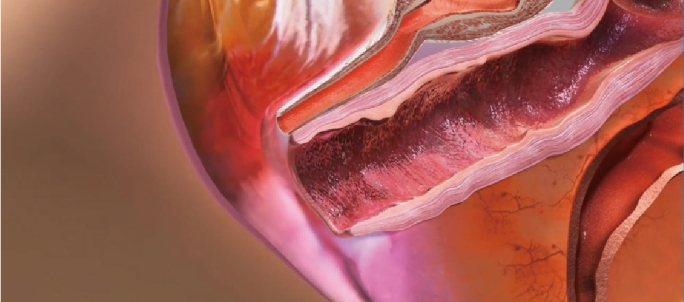

Thermal stimulation of entire vaginal wall layer

Immediately after treatment, shrinkage of the vaginal skin fibers occurs. In addition, collagen growth is promoted and the vaginal wall becomes resilient and thick. Changed Vaginal structure after treatments makes its whole conditions better.

Before

After

Effect of Laser Treatment Collagen Stimulation

- Vaginal Remodeling

- Vaginal Dryness

- Sexual Dissatisfaction

- Pelvic Organ Prolapse

- Urinary Incontinence

Before the treatment Loosen vagina inner wall